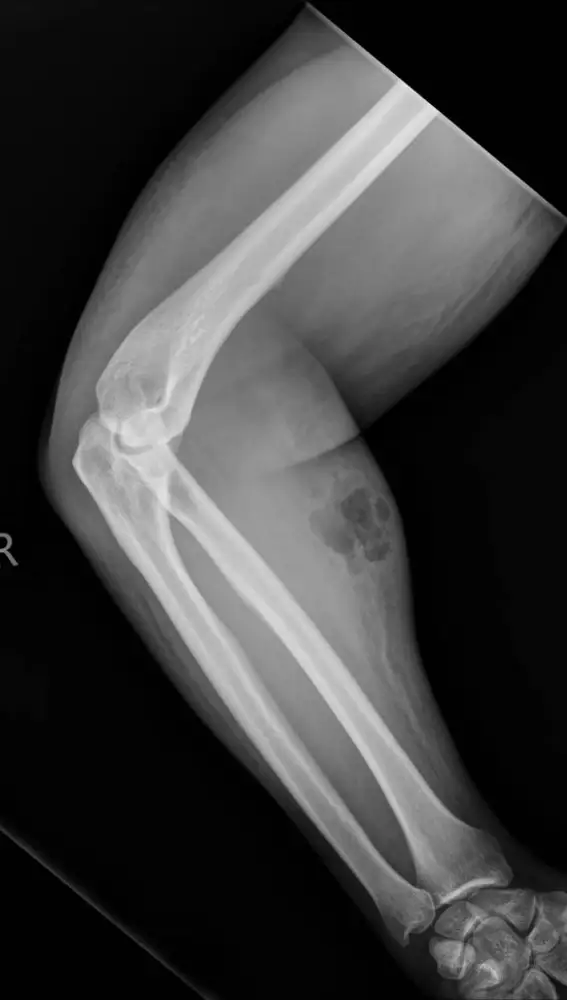

Este "remedio" no solo no le ayudó a solucionar su dolor de espalda si no que le provocó complicaciones en el brazo donde se inyectaba el esperma con una aguja que él mismo había comprado por Internet, ya que introducía aire bajo la piel provocándole unas consecuencias muy peligrosas para la salud.